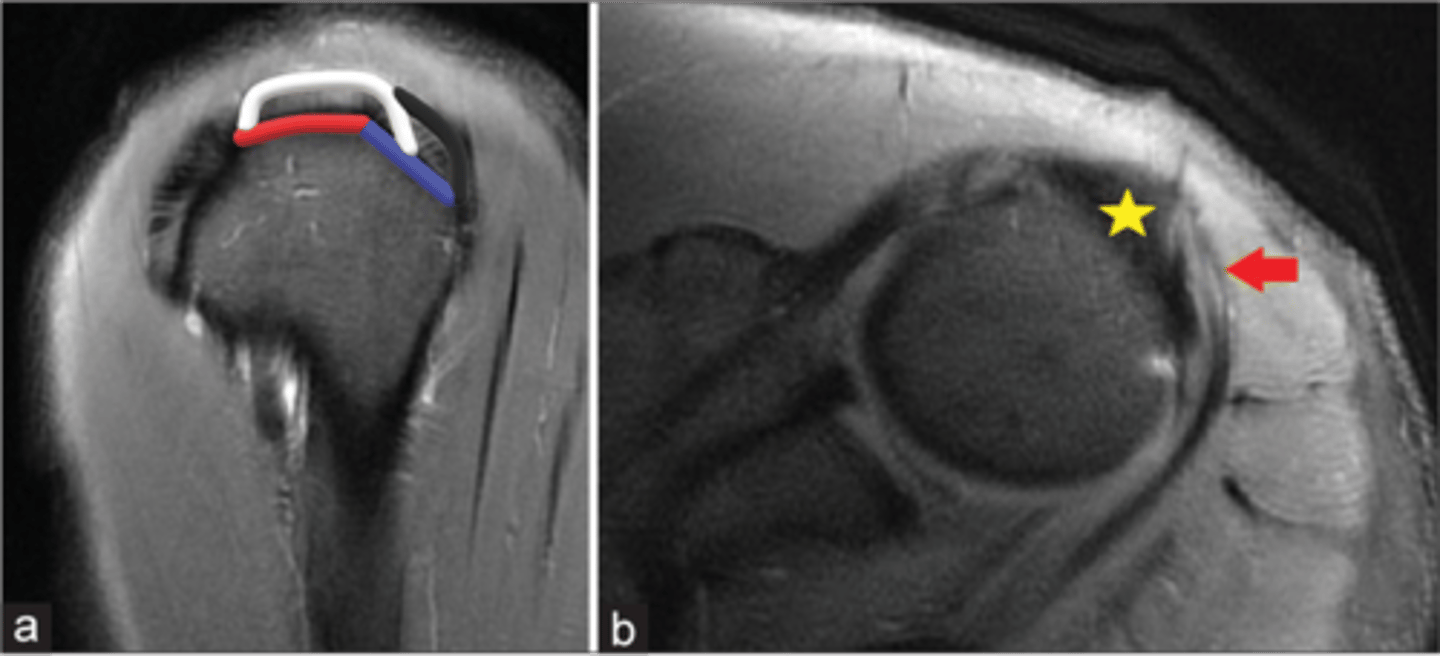

This system allows us to classify partial tears of the rotator cuff:

1 = Bursal-sided tear

3 = Intra-substance tear (in the middle of the tendon itself)

5 = Articular-sided tear

Note: we can also identify "delamination," where these fibers separate from one another, which would also be considered a partial tear

Why is understanding this image important?

Left image: bursal-sided tear w/ SOME fibers still intact

RIght image: bursal sided AND intrasubstance tears

NOTE: our concern is these partial tears will progress to full tears

What are these images depicting w/ the rotator cuff? What is our concern?